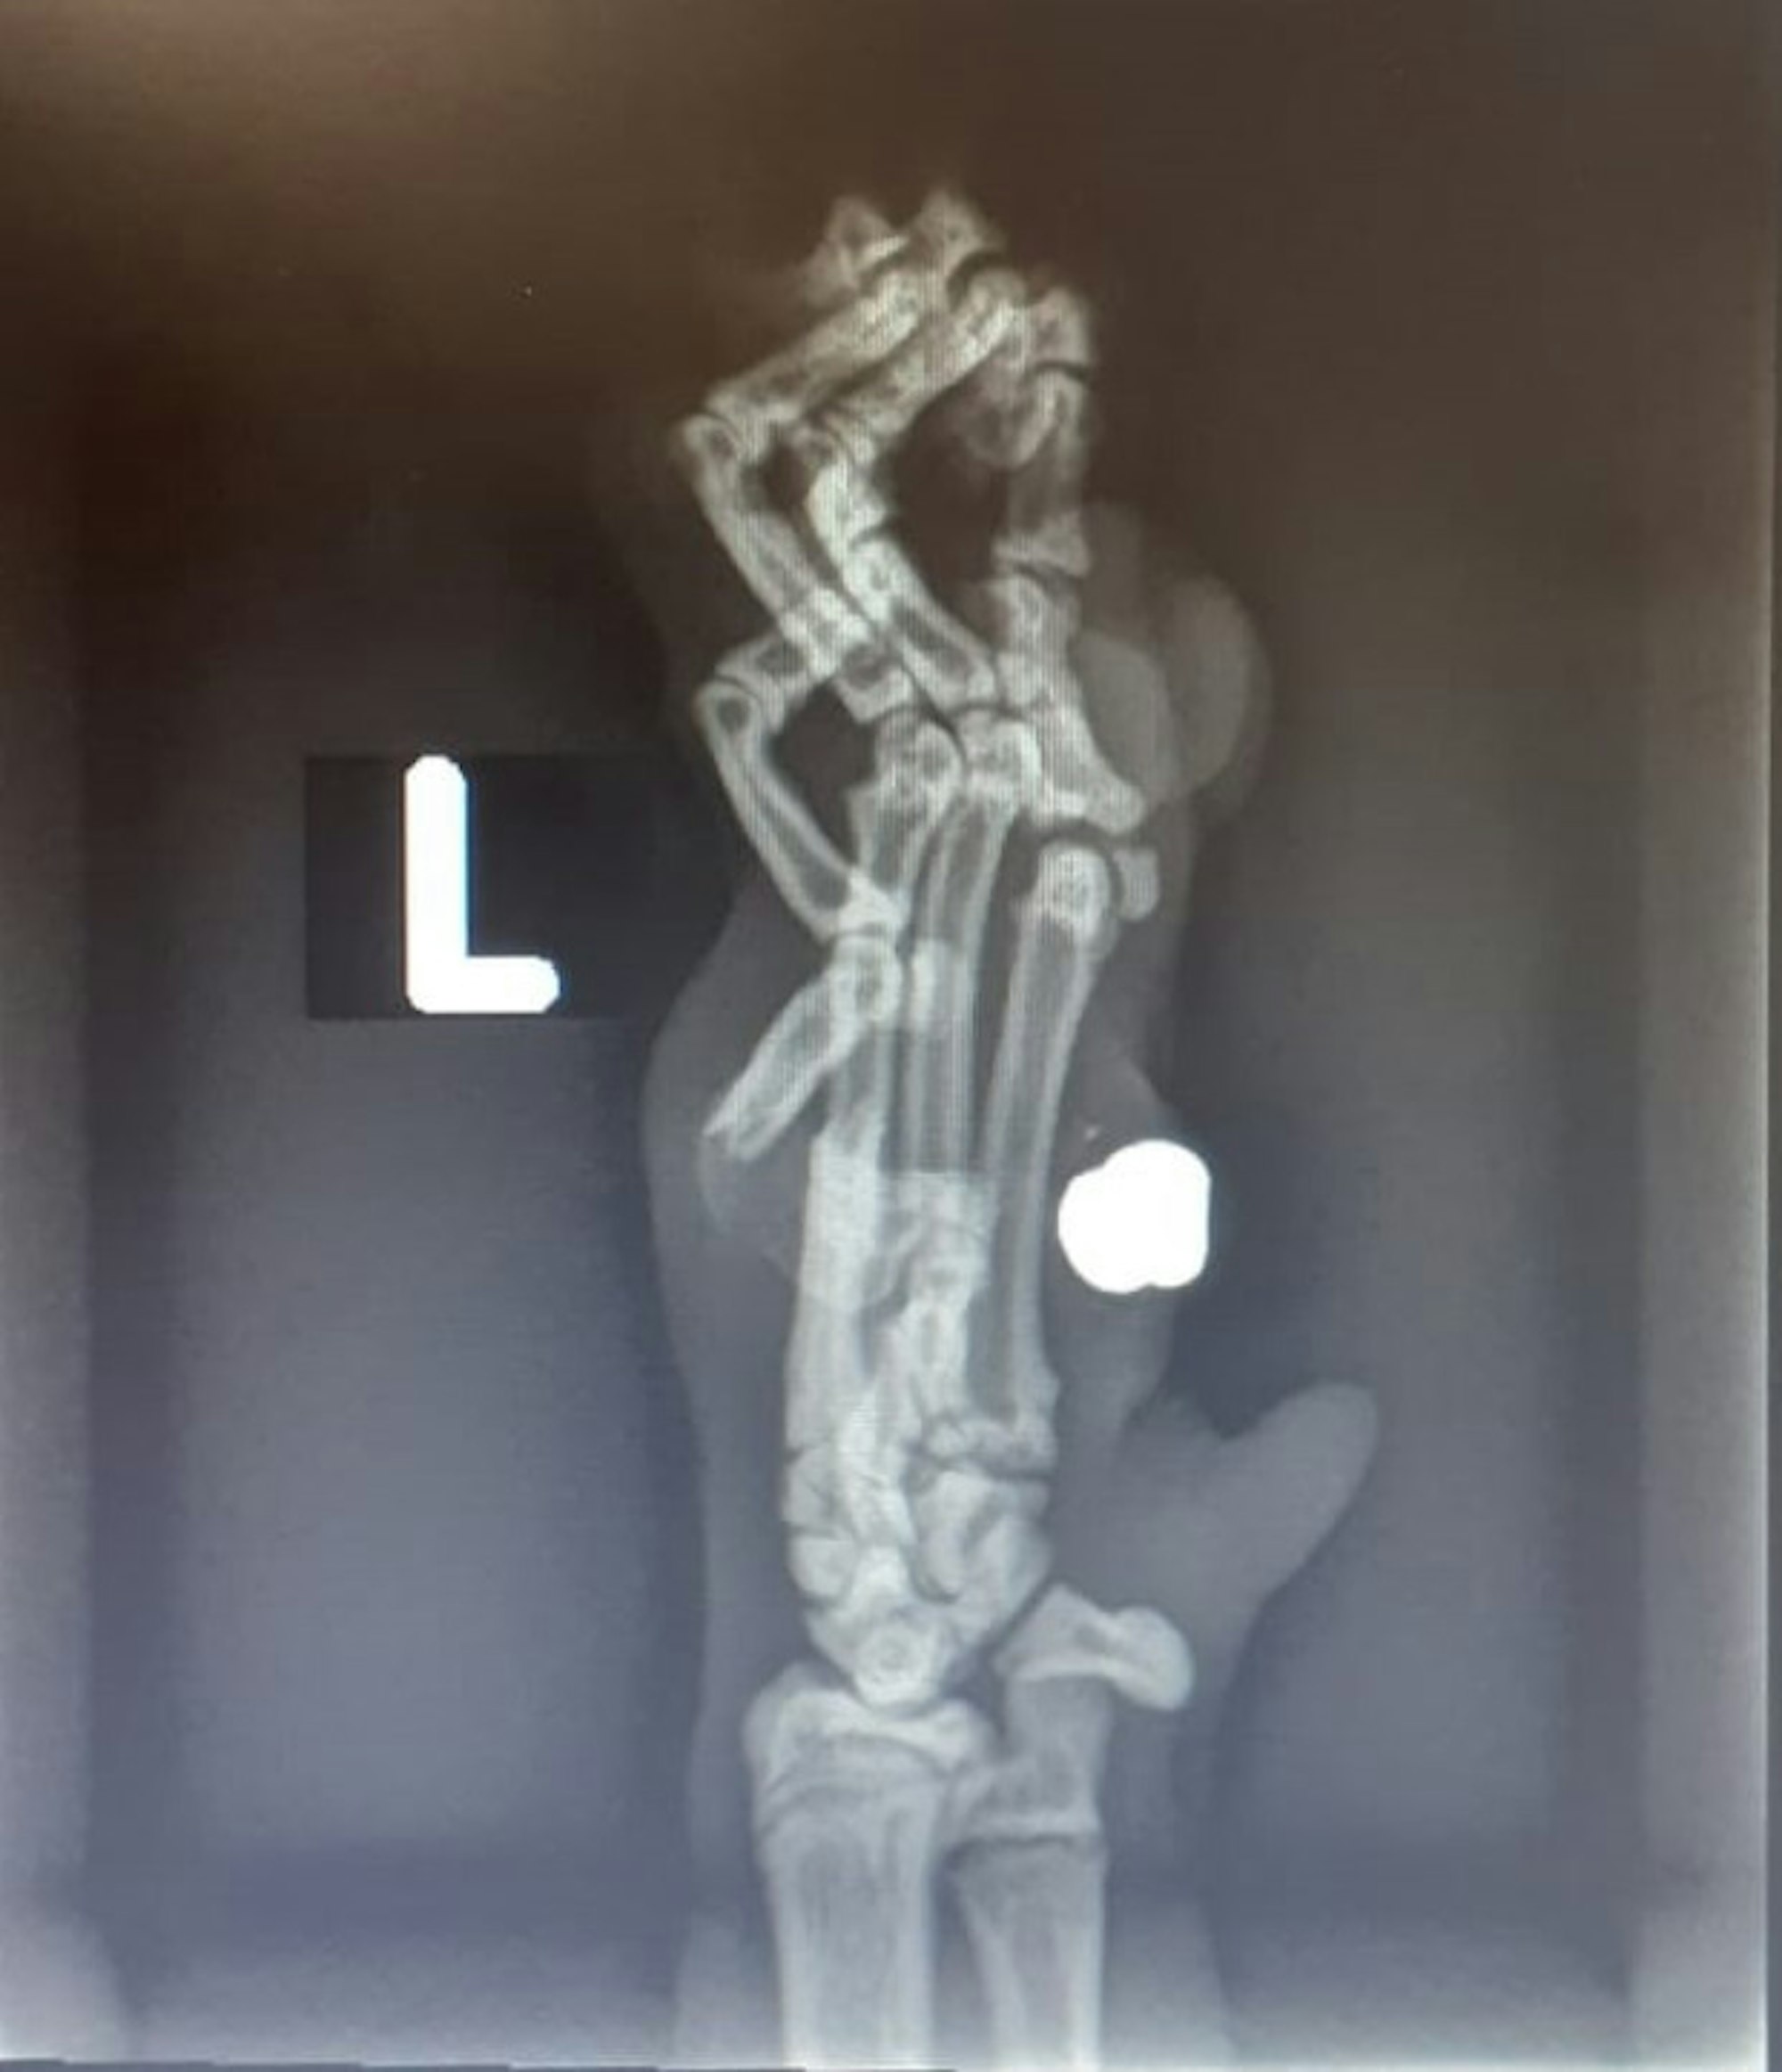

Bergheim-Quadrath-Ichendorf – Humpelnd auf drei Pfoten kam Maui von ihrem morgendlichen Kontrollgang am Auerweg zurück. Die vierte Pfote war geschwollen und verwundet. Beim Tierarzt stellte sich heraus, dass in Mauis linkem inneren Finger ein Diabolo-Projektil steckte. Maui war mit Luftgewehr-Munition beschossen worden.

Zunächst dachte Halterin Roswitha Tippach an einen Biss. Erst der Besuch in der Tierklinik und ein Röntgenbild brachten später, als die Schwellung nicht abklingen wollte, die Gewissheit, dass ein kleines Geschoss in der Pfote steckte und ein Fingerknochen durchschlagen war.

Eine Röntgenaufnahme zeigt die Verletzung der Katze.